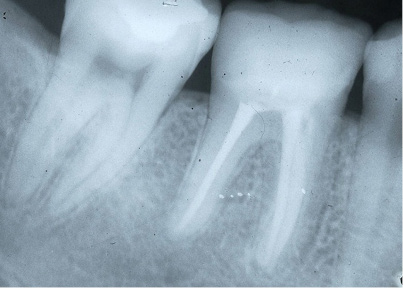

Fig. 4c X-ray control after 10 years (a=years).